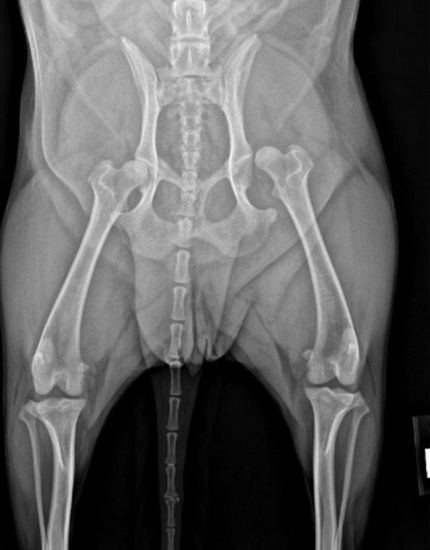

Canine patient with a traumatic hip luxation treated with a TightRope Hip Toggle